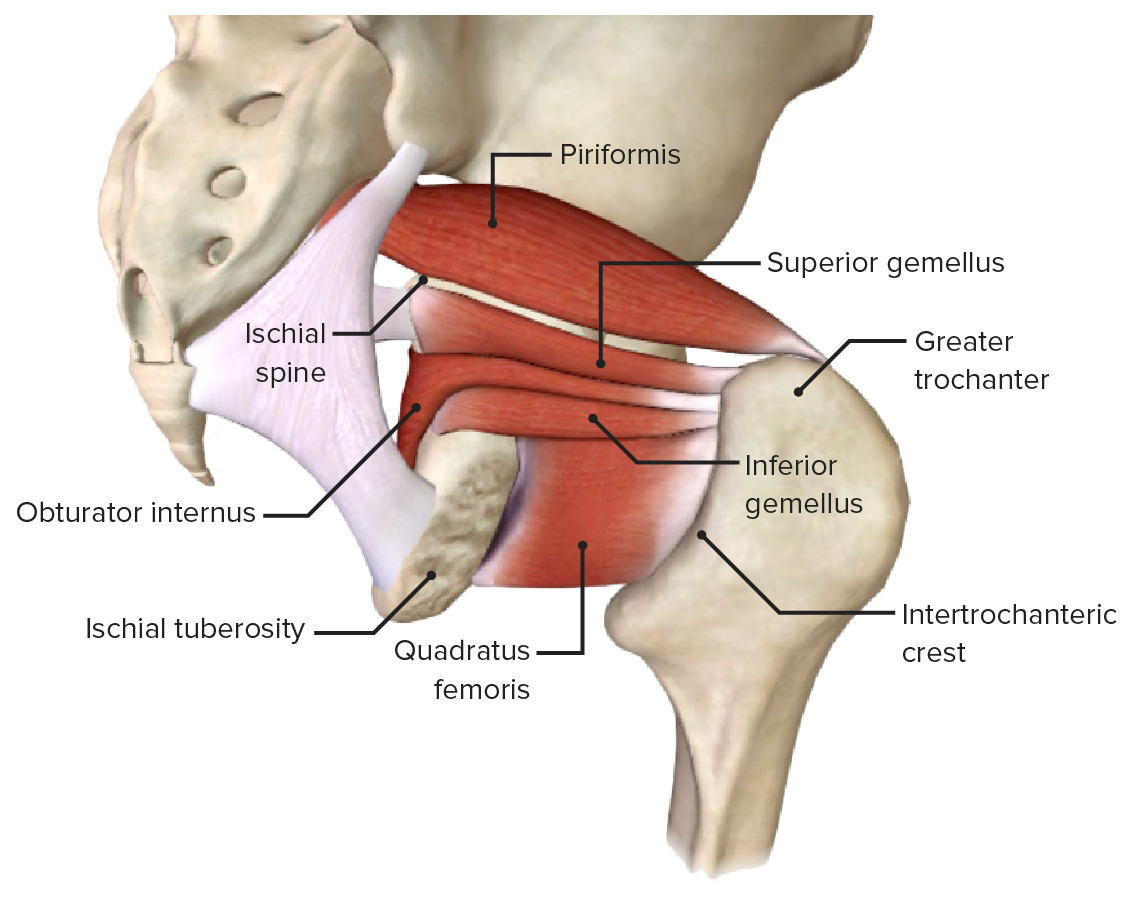

Анатомия мышц: Пириформис